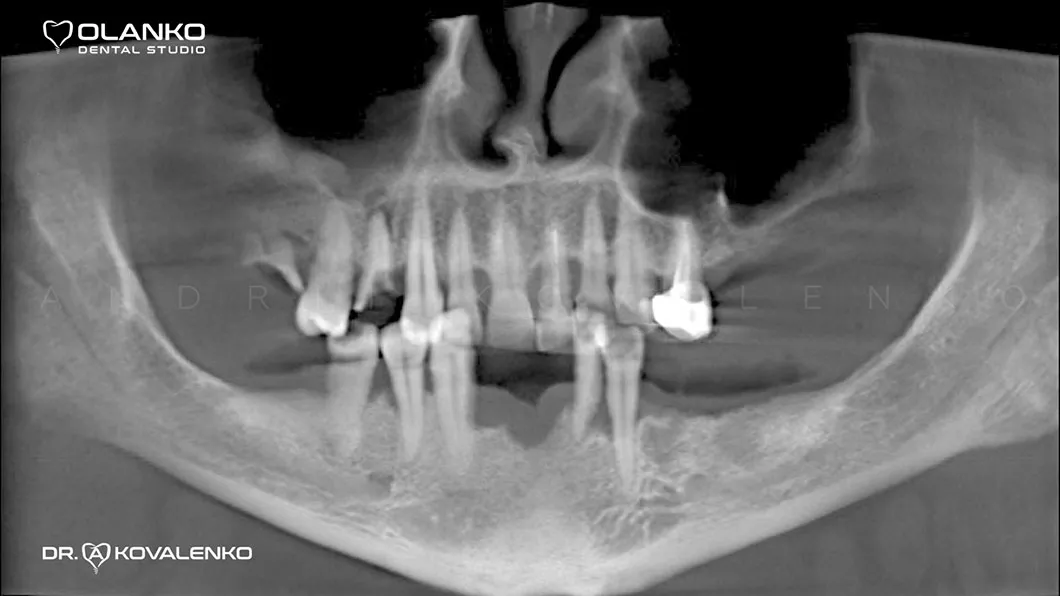

Пациент обратился с жалобами на нарушение функции жевания и эстетики, в связи с отсутствием зубов, а также значительной подвижности зубов на нижней челюсти.

Лечение: пародонтологическое лечение (лечение дёсен). Лечение кариеса. Лечение корневых каналов.

Удаление зубов на верхней и нижней челюсти с одномоментной установкой зубных имплантатов по шаблону. Костная пластика.

Ситуация до: